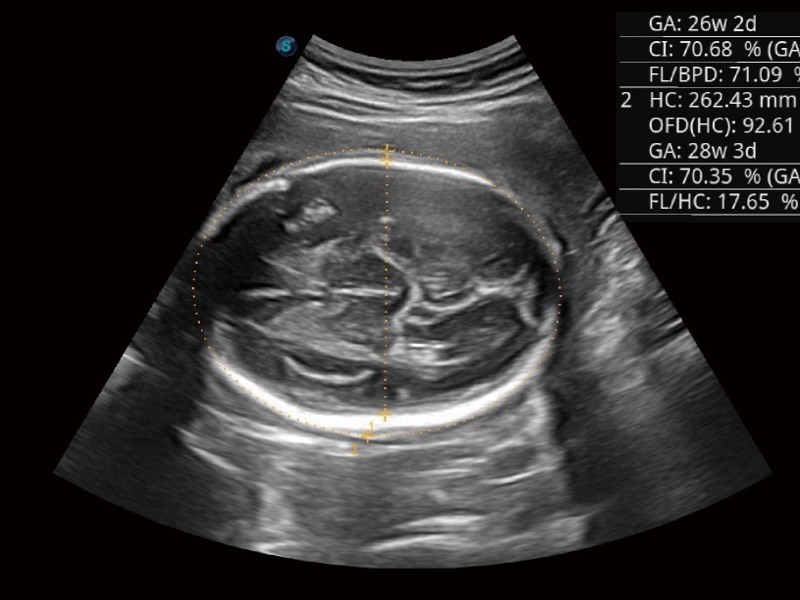

• 妇产科应用

超声检查得益于实时性、经济性、便捷性,目前广泛的应用于临床工作中,超声检查设备已成为帮助临床医生轻松地完成诊断工作的好伙伴。P20 Plus集成了一整套包含了腹部、心血管、小器官、妇产科等全面临床应用功能,轻松应对各种临床问题。